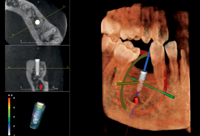

Vantaggi della radiografia 3D

La radiografia 3D offre al dentista informazioni dettagliatissime per una diagnostica più esatta e una maggiore precisione di trattamento. La radiografia 3D offre una visione completa sull’anatomia maxillo-facciale, quasi da ogni angolo e in quasi ogni prospettiva. Informazioni che non vi sarebbero mai disponibili con le sole immagini in 2D.